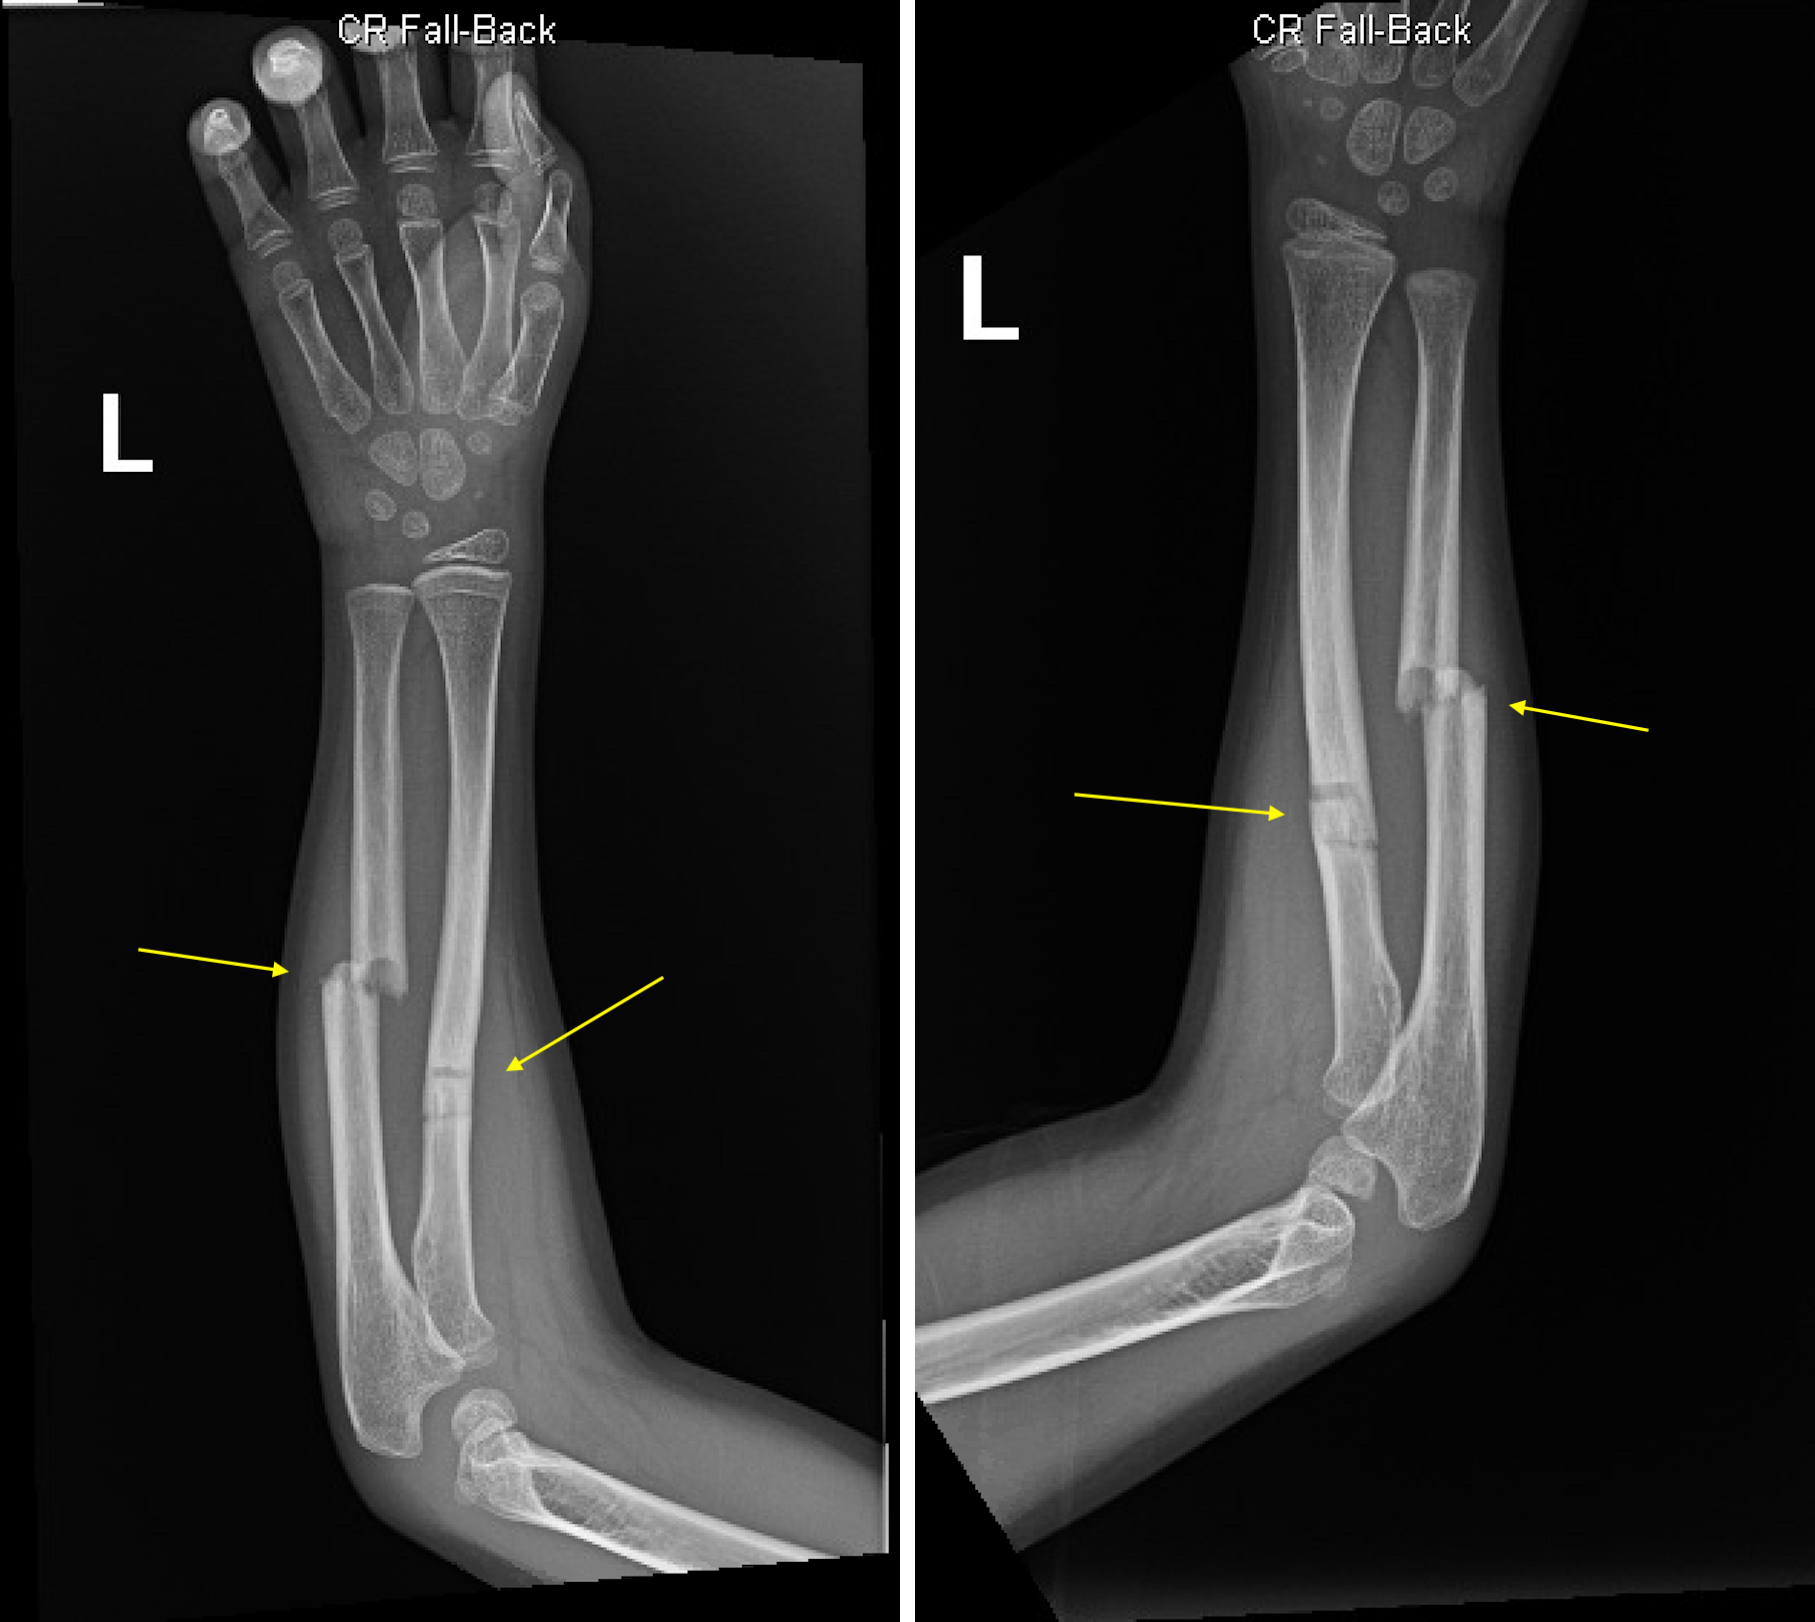

1st stage (fracture repair)

hematoma forms

2nd stage (fracture repair)

soft (fibrocartilaginous) callus forms

3rd stage (fracture repair)

hard (bony) callus forms

4th stage (fracture repair)

remodeling begins

open (compound) fracture

closed (simple) fracture

displaced fracture

transverse fracture

oblique fracture

compression fracture

greenstick fracture

spiral

communiated fracture